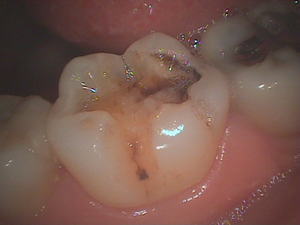

症例です。

メタルインレーの脱離で来院されました。

黒くなっています。

虫歯で柔らかくなっている部分(軟化象牙質)を取ります。

よーく見ると、歯にヒビが入っています。

このようなヒビ(クラック)は日常臨床ではよく観察できます。

歯と歯はものすごい力でぶつかり合っています。

ナイトガードで力のコントロールを図る必要があります。